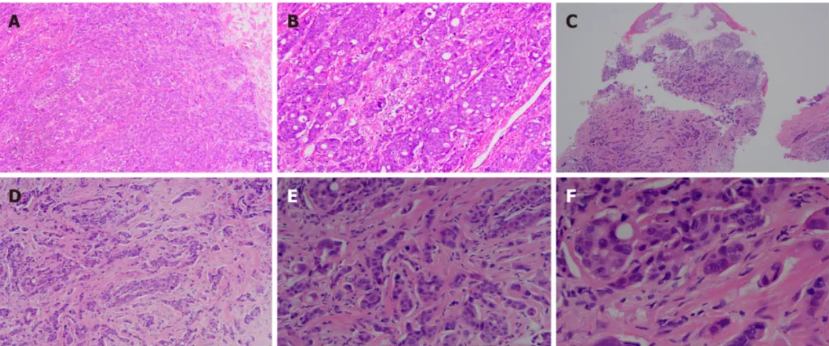

为进一步明确阴茎肿块性质,患者接受了冠状沟处三个肿块的局部手术切除。切除肿块的组织病理学检查显示为低分化腺癌,与原发结肠肿瘤一致(图3)。免疫组化检查显示CDX2、CK20和SATB2阳性表达,表明阴茎肿块起源于结肠(图4)。

图3. 结肠肿块与阴茎肿块的苏木精-伊红染色